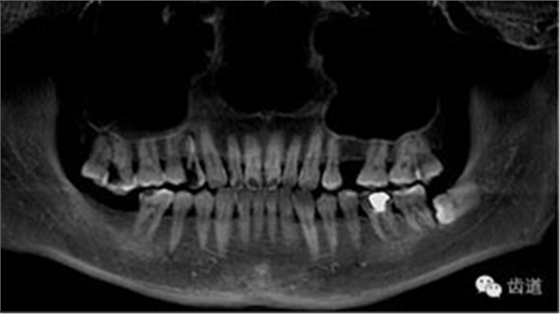

本病例為右上第一前磨牙三根管疑難病例,首診及二診由重慶醫(yī)科大學(xué)附屬口腔醫(yī)院牙體牙髓科下級(jí)醫(yī)生處理,因根管遺漏未能處理轉(zhuǎn)診上級(jí)醫(yī)生鄭玉琪老師進(jìn)行顯微根管治療。本病例是不可多得的如何避免遺漏根管及如何治療遺漏根管的帶教根管治療病例之一。

好的開(kāi)始就是成功的一半。通過(guò)CBCT了解根管的位置,形態(tài),方向。

檢查顯示:近頰及腭根充填恰填,遠(yuǎn)頰根管內(nèi)有少許充填物影像。根尖明顯低密度影像。

上頜第一前磨牙:87%為雙根管,其次為單根管,另有2.4%為三根管,側(cè)支根管發(fā)生率49.5%;